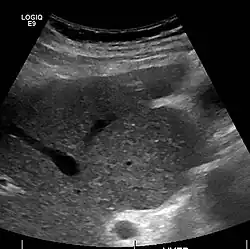

Imaging

Ultrasound is routinely used in the evaluation of cirrhosis.[45] It may show a small and shrunken liver in advanced disease. On ultrasound, there is increased echogenicity with irregular appearing areas.[64] Other suggestive findings are an enlarged caudate lobe, liver surface nodularity[65] widening of the fissures and enlargement of the spleen.[66] An enlarged spleen, which normally measures less than 11–12 cm (4.3–4.7 in) in adults, may suggest underlying portal hypertension.[67] Ultrasound may also screen for hepatocellular carcinoma and portal hypertension.[45] This is done by assessing flow in the hepatic vein.[68] An increased portal vein pulsatility may be seen. However, this may be a sign of elevated right atrial pressure.[69] Portal vein pulsatility is usually measured by a pulsatility index (PI).[68] A number above a certain value indicates cirrhosis (see table below).